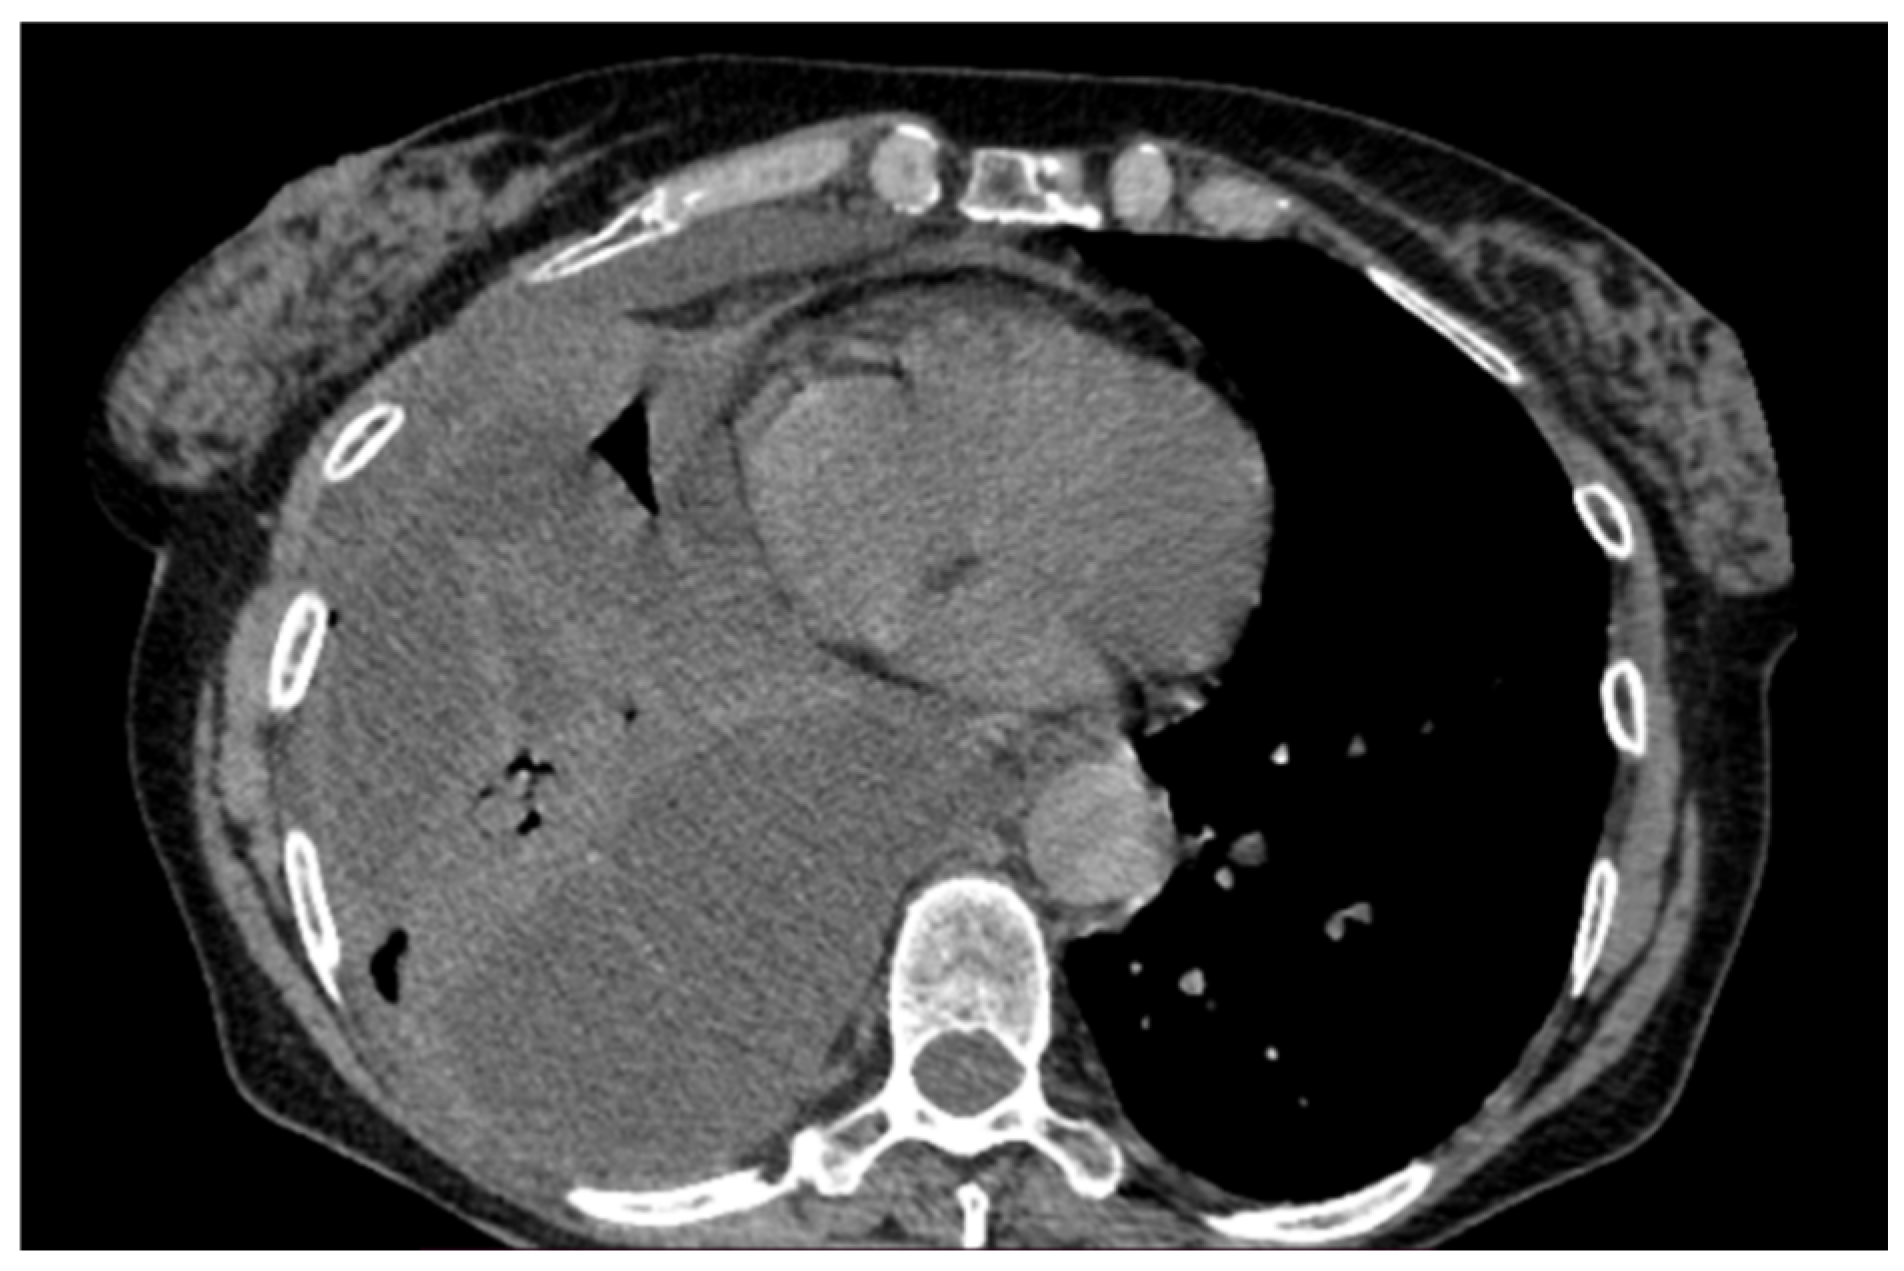

Figure 6. Chest CT scan of the mediastinal window in the coronal (A) and axial (B) plane, showing a large right pleural effusion, occupying almost the entire hemithorax with organized appearance. There is also a complete right lower lobe atelectasis and almost-complete right middle and upper lobe atelectasis with sparing of anterior sectors.

A 61-year-old female patient with obesity, discoid lupus, bipolar disorder, arterial hypertension, and hypothyroidism was admitted to our Respiratory Unit for respiratory failure and evidence of a large complex PEff on her chest CT, which also revealed complete atelectasis of the right lower lobe (RLL) and almost-complete atelectasis of the middle lobe (ML) and right upper lobe (RUL) (Figure 6). There was also a solid tissue surrounding the right main bronchus and its main branches, which was suspected to be neoplastic. It had a central hypodense area consistent with necrosis.

Peripheral enhancement of the pleural layers was also observed.

A chest drain was placed, with the collection of purulent fluid. High-flow oxygen therapy was initiated, and the patient was treated with broad-spectrum antibiotics (vancomycin + piperacillin/tazobactam). The fluid was analyzed and was positive for Streptococcus intermedius and showed typical chemical and physical characteristics of exudates, so a diagnosis of a right pleural empyema was made. As a result, 3 days of treatment with intrapleural urokinase was initiated. The urokinase was administered in a daily single dose of 100,000 UI diluted in 50 mL of saline solution. At the end of the IPFT, a chest US was performed. It showed a decrease in effusion with a single loculation that extended over a width of three intercostal spaces. A chest CT was also performed, which confirmed the decrease in PEff and showed the re-expansion of RUL and ML and the partial re-expansion of RLL. The increased density formation described earlier was no longer evident. The patient was then referred for uniportal VATS to complete the toilette and obtain biopsies. Multiple pleural biopsies were performed. The results were consistent with chronic pleuritis, and no elements were noted that were suspicious in terms of malignancy. The biopsy showed fibrous tissue with hemosiderin-laden macrophages and scattered inflammatory cells. No neoplastic cells could be observed. Thus, a malignant lesion could be excluded. The chest tube was later removed, a chest CT was performed, and the patient was finally discharged (Figure 7).

This case describes the possible use of IPFT, before considering surgery, in a patient with a stage 2 fibrinopurulent empyema. Fibrinolysis was propaedeutic to VATS, which was performed to complete the decortication and obtain tissue samples. Indeed, patients receiving intrapleural fibrinolytic therapy require surgical referral in up to 10% of cases.